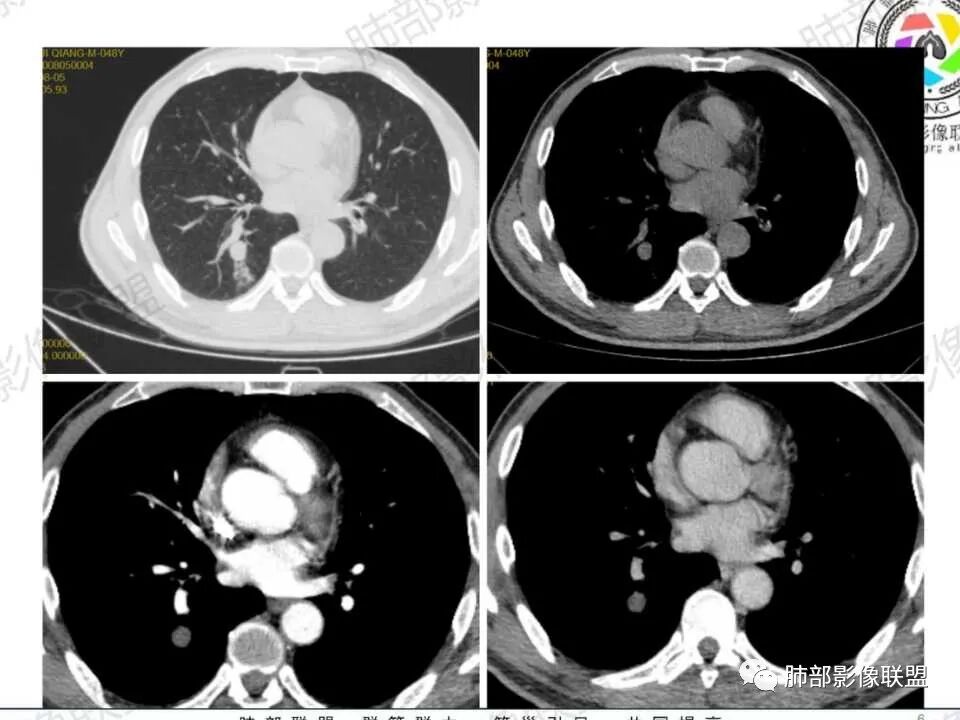

男性病人48岁,既往有糖尿病的病史,影像学表现,右肺下叶后段类圆形的小结节病灶 ,边界比较光整,内见小空洞影 ,病灶远端见小片状的渗出性病灶,增强扫描病灶轻度的强化。病灶在治疗的过程中短期内有增大。整体病灶表现为一个光整结节+远端阻塞性肺炎+小空洞+轻强化,周围无卫星病灶,考虑感染性病变,隐球菌感染?结核次考虑。

右肺下叶结节,边缘光整,密度均匀,伴阻塞炎症,增强无强化,抗感染一周复查效果差,结节内小空洞,阻塞明显,胸膜增厚,糖尿病病史,首先考虑结核,隐球菌待排

糖尿病病史,右肺下叶结节,边缘光整,密度欠均匀,远端阻塞炎症,增强强化不明显,抗感染一周复查,结节较前增大,内出现小空洞,阻塞明显,胸膜增厚,首先考虑结核,隐球菌待排。

3.近背段支气管开口附近结节密度不甚均匀,未见钙化或脂质密度区。边界清楚光整,内侧平直,未见典型深分叶及毛刺,增强扫描轻度强化。

4.哌拉西林、左氧氟沙星等治疗一周后,较大结节影及外围病灶范围均见增大。

5.背段支气管于结节内侧份“旁现侧出”,管壁完整,管腔少量分泌物,近乎疏通状态。结节内隐约出现微小含气空腔。